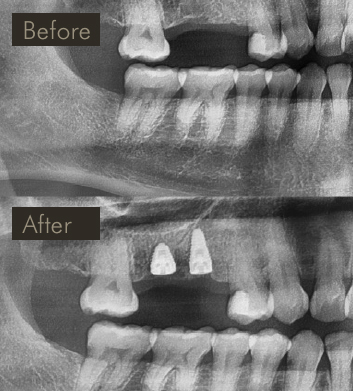

» X-ray image showing before & after placement of implants in upper right to replace 2 missing teeth.